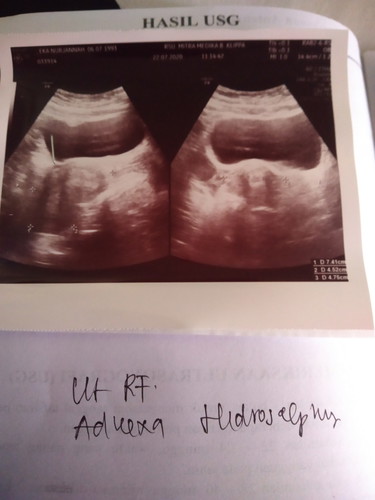

Assalamualaikum, selamat siang bunda Bun, saya ingin bertanya pernahkah bunda2 di sini mengalami pembengkakan di rahim? Kemarin saya USG kata nya ada pembengkakan di rahim saya , yg menyebabkan saya sulit hamil. Jika salah boleh bertanya bunda di sini yg mengalami hal serupa bisa kah hamil?